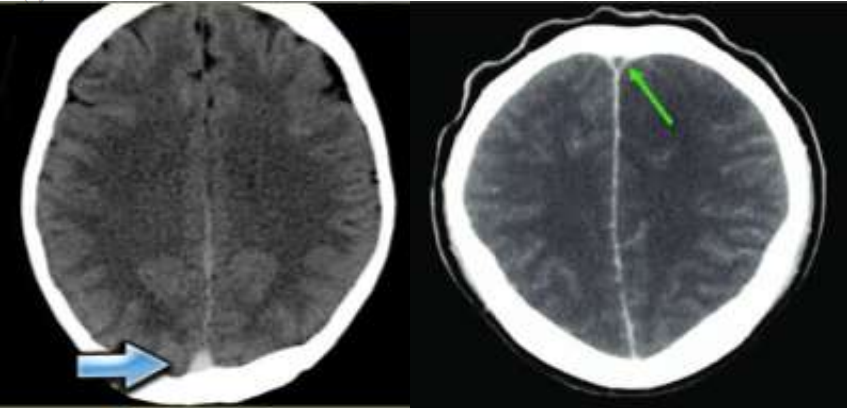

Cắt lớp vi tính sọ não bình thường trong 30% các trường hợp CVT, và hầu hết dấu hiệu là không đặc hiệu. Cắt lớp vi tính sọ não có các dấu hiệu trực tiếp của CVT như sau:

• Chụp cắt lớp vi tính (CT) không cản quang: dấu hiệu delta đặc, có biểu hiện tăng đậm độ hình tam giác bên trong xoang dọc trên. Hình ảnh nhồi máu não không phù hợp với các khu vực tưới máu của động mạch não. Cũng có thể thấy hình ảnh của nhồi máu kết hợp chảy máu.

• Chụp cắt lớp vi tính tĩnh mạch(CTV) não: dấu hiệu delta rỗng là hình ảnh đặc trưng của huyết khối khoang dọc trên, do tăng tỉ trọng của các tĩnh mạch bàng hệ trong thành của xoang dọc trên, xung quanh cục huyết khối không ngấm thuốc cản quang. Hình ảnh huyết khối gây choán chỗ hay tắc xoang tĩnh mạch não.

Hình 1: Dấu hiệu delta đặc trên phim CT thường (a) và dấu hiệu delta rỗng trên phim CT tiêm thuốc cản quang (b)

Hình 2: Tổn thương nhồi máu không theo phân vùng cấp máu của động mạch kết hợp chảy máu não (c), Hình mất liên tục ở xoang tĩnh mạch dọc trên (d) ở người bệnh tại Bệnh viện Bạch Mai